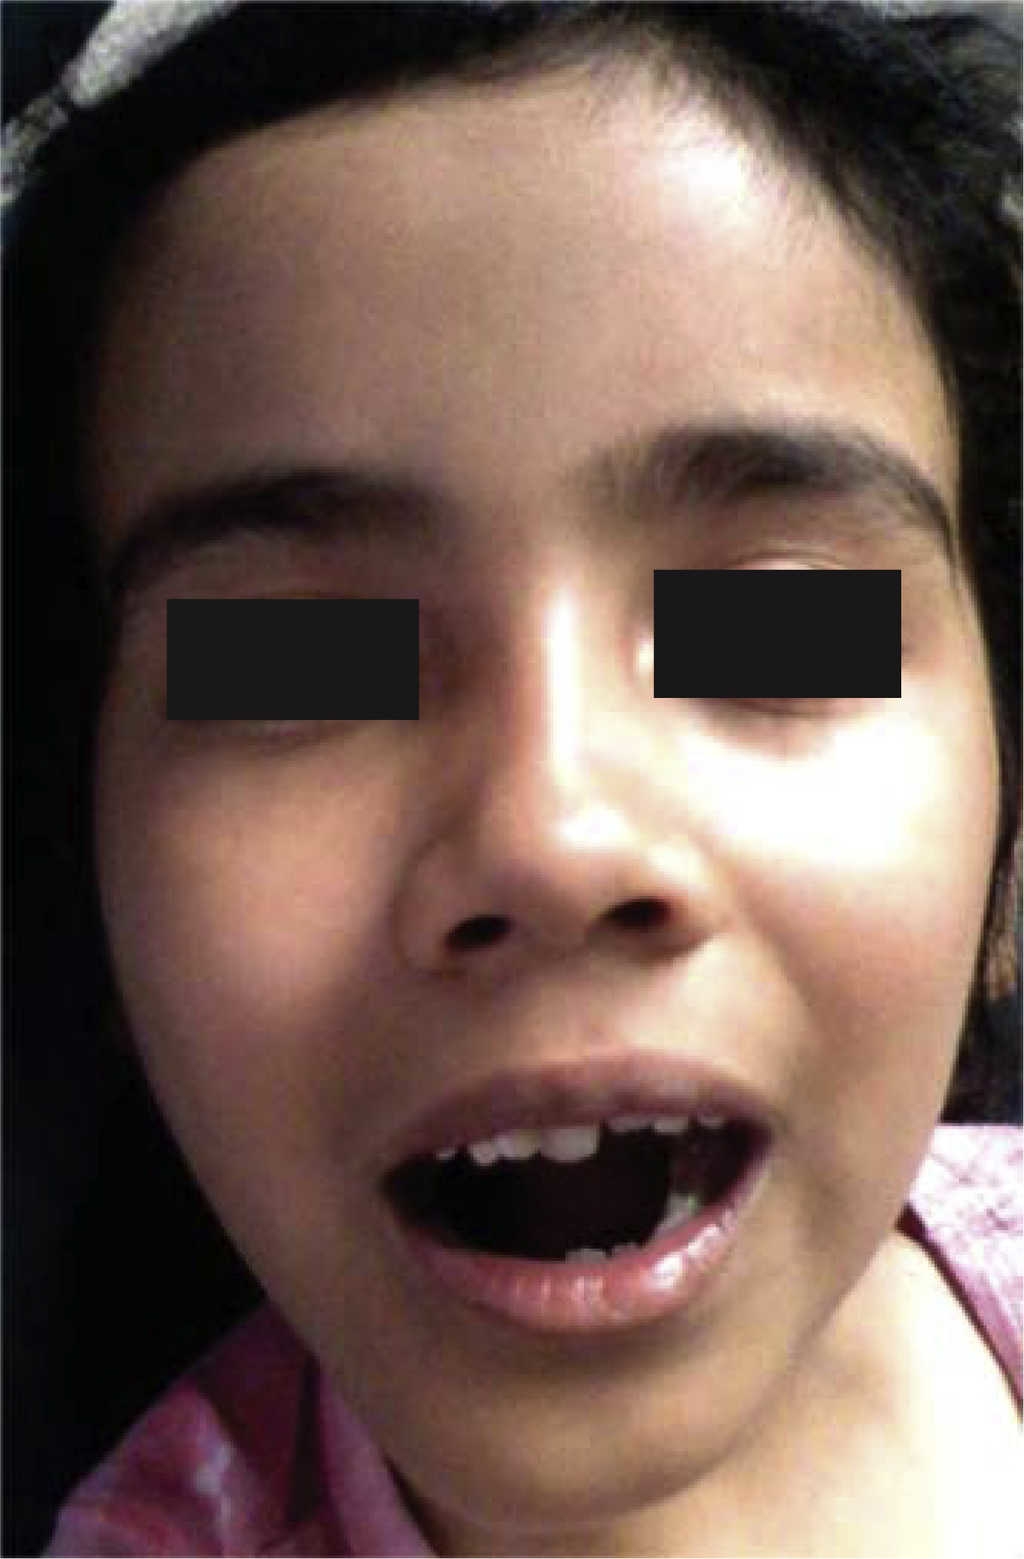

Paciente femenina de seis años de edad la cual presenta aumento de volumen a nivel mandibular lado derecho, de cuatro meses de evolución, con crecimiento rápido y ligero dolor a nivel de la lesión (Figura 1). Intraoralmente se observa expansión de corticales óseas mandibulares a nivel de molares.